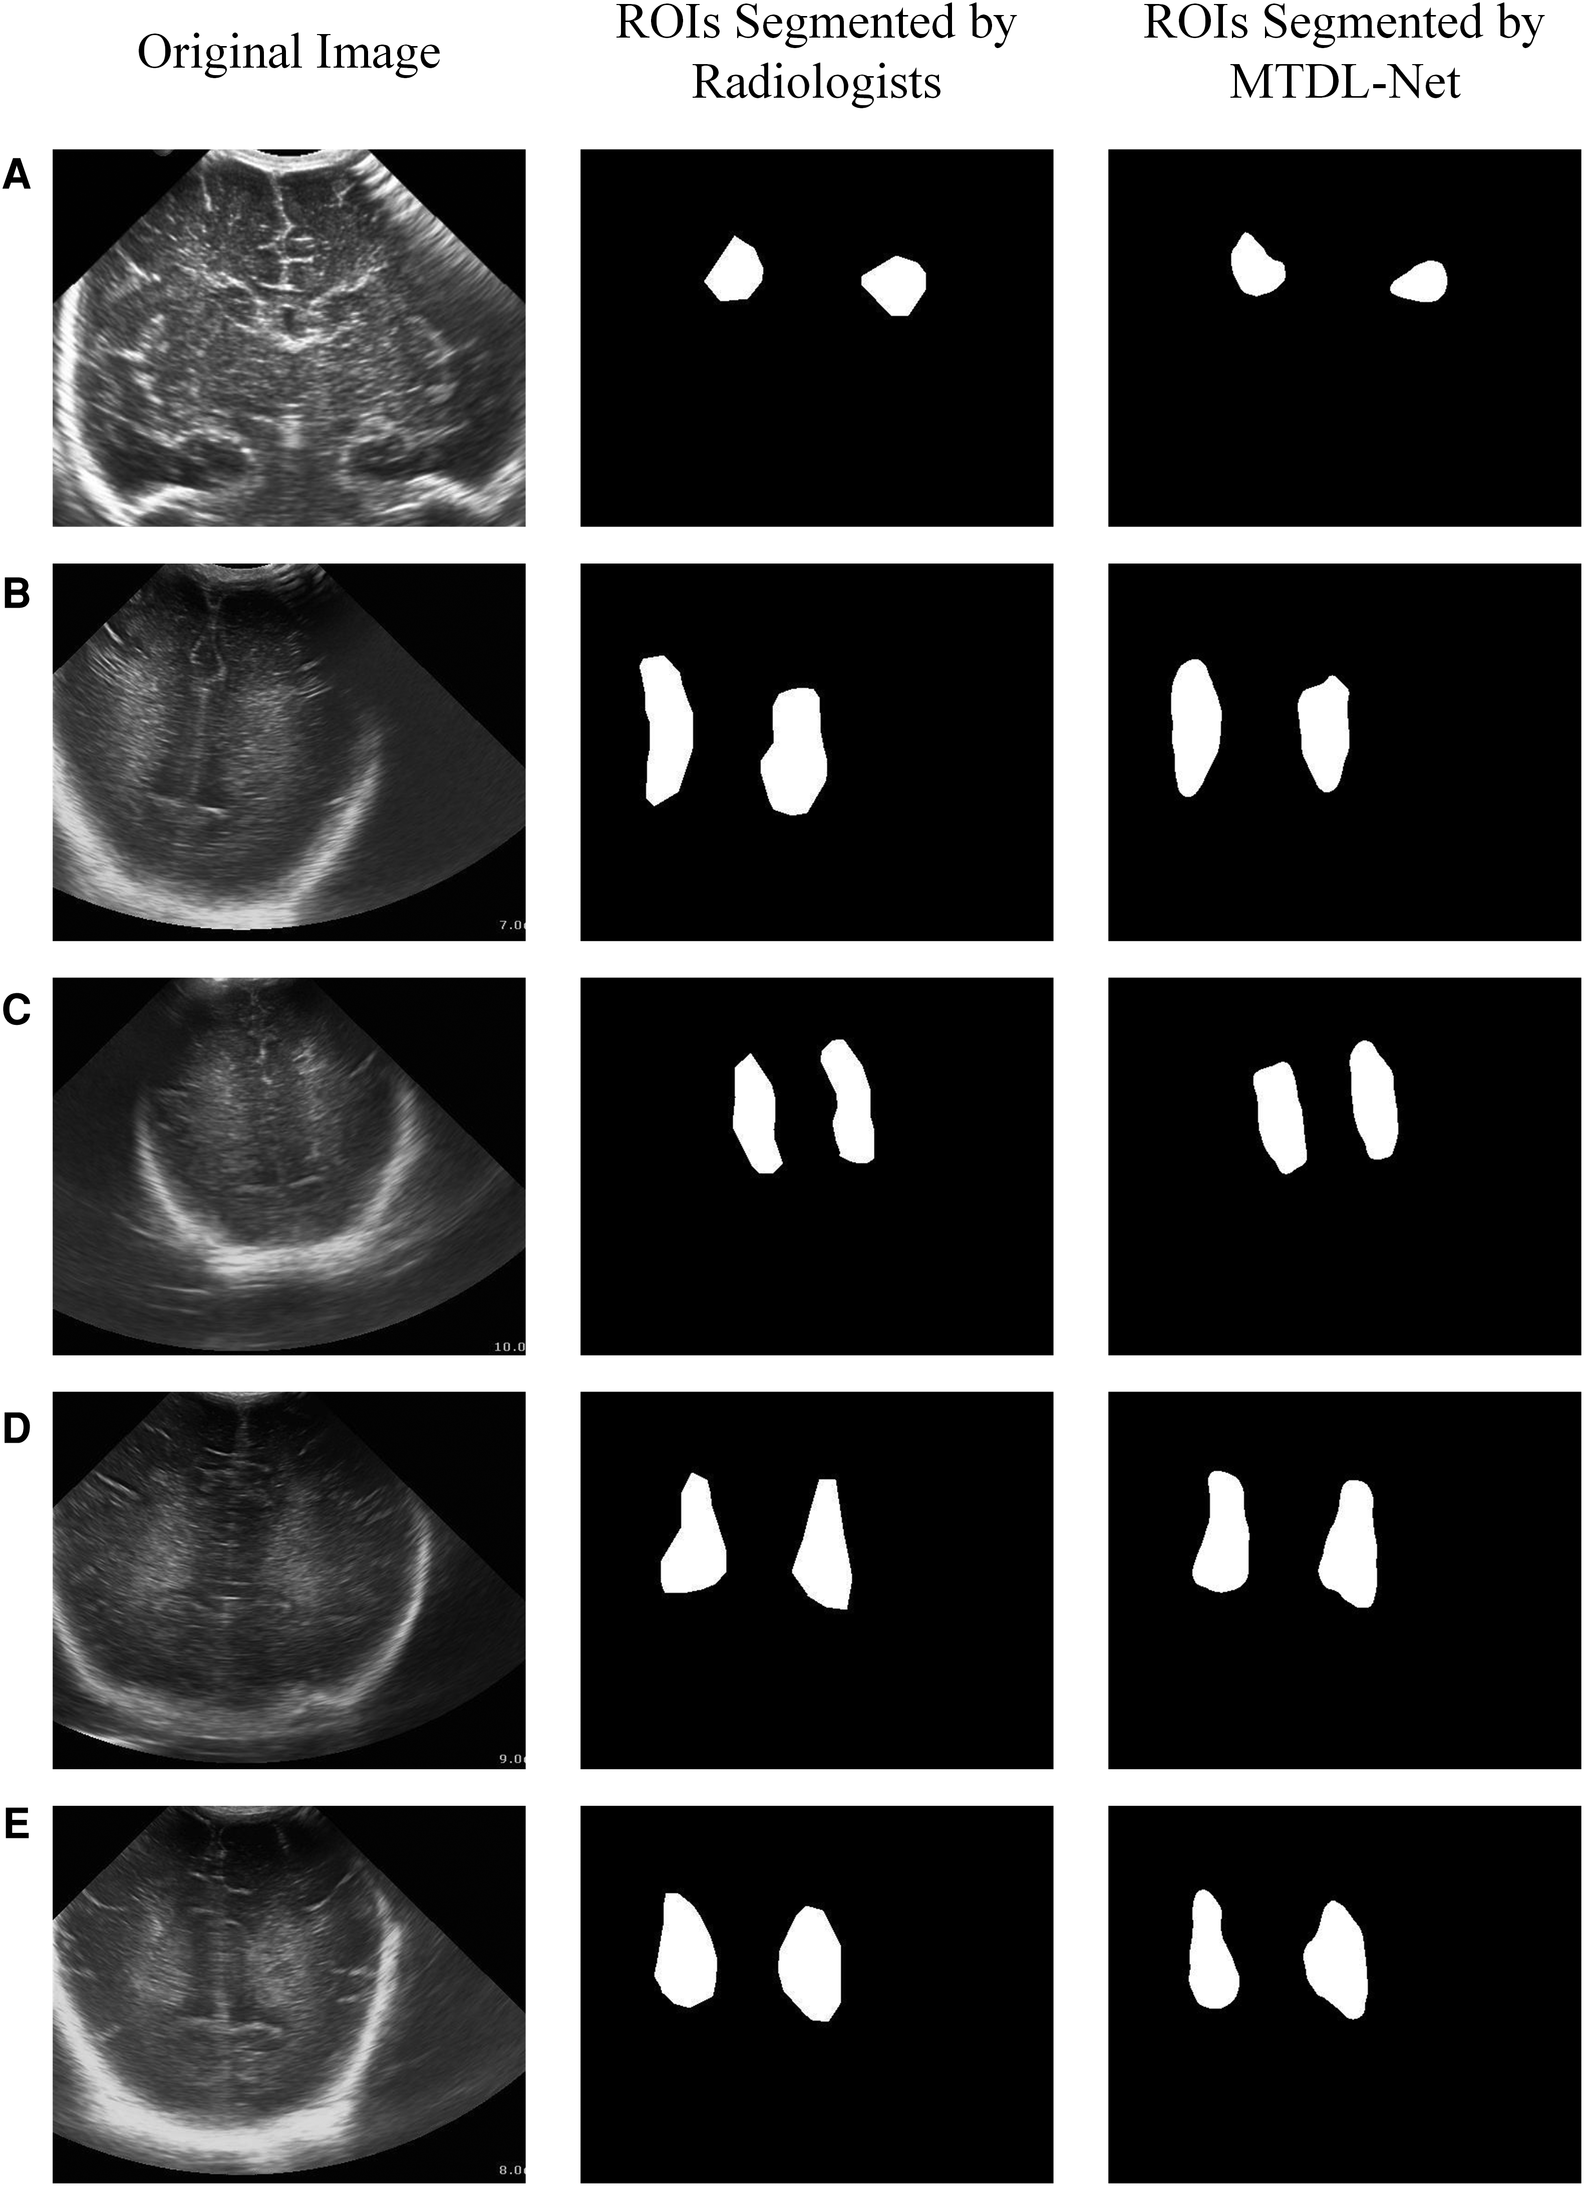

We used training cohort to train the parameters in MTDL-Net, and then used testing cohort to evaluate the segmented results and prediction results. Part of the segmented results shows in Figure 9. As shown, the segmented result by MTDL-Net achieved better performance than SDL-Net. Table 4 shows the results of our methods. It can be observed that segmented result on testing cohort has an overall Dice of 0.78, an accuracy of 0.81, and an IoU of 0.82.

Figure 9

White matter ROIs segmented by MTDL-Net.

In the WMI prediction task, we sent segmented result by MTDL-Net into ultrasound radiomics diagnostic system to predict WMI as a comparison. The result is listed in Table 5. As shown, AUC of our method reached 0.863 in the testing cohort, while AUC of SVM based C-SVC was 0.829. The ROC curves of our method and SVM based C-SVC in testing cohort is shown in Figure 10.